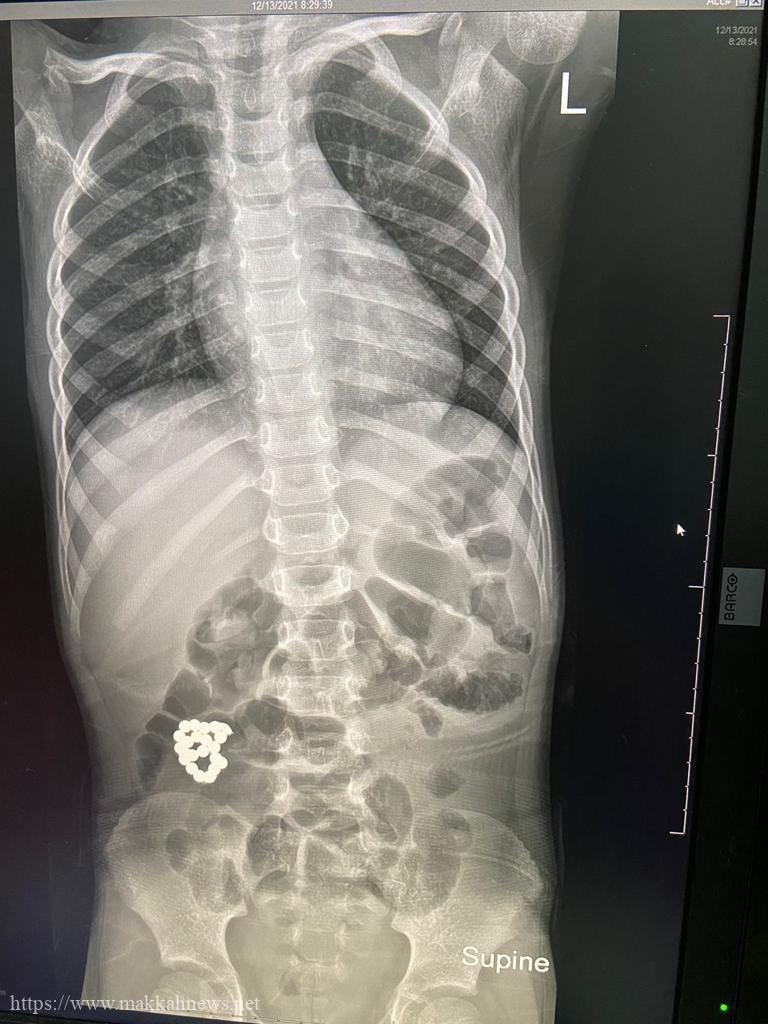

جدة : تمكن فريق طبي بمستشفى الملك عبد العزيز بجدة بقيادة بروفيسور جراحة الأطفال الدكتور عمر منصور من إنقاذ حياة طفل في السادسة من عمره ، حضر لطوارئ المستشفى يشتكي من ألم في البطن ملازمه منذ ٤ أيام و ازدادت الآلام مع الوقت ، حيث تم عمل الفحوصات اللازمة ، و أظهرت صور الأشعة وجود جسم غريب في الأمعاء .

و على الفور تم إدخال الطفل لغرفة العمليات واستخراج الجسم الغريب ، كما تضرر جدار الأمعاء ، حيث تم استئصال الأجزاء المتضررة في عملية أستغرقت ساعتين و نصف تكللت بالنجاح و لله الحمد و الطفل في حالة مستقرة بفضل الله ، في قسم التنويم العادي و حالته في تحسن .